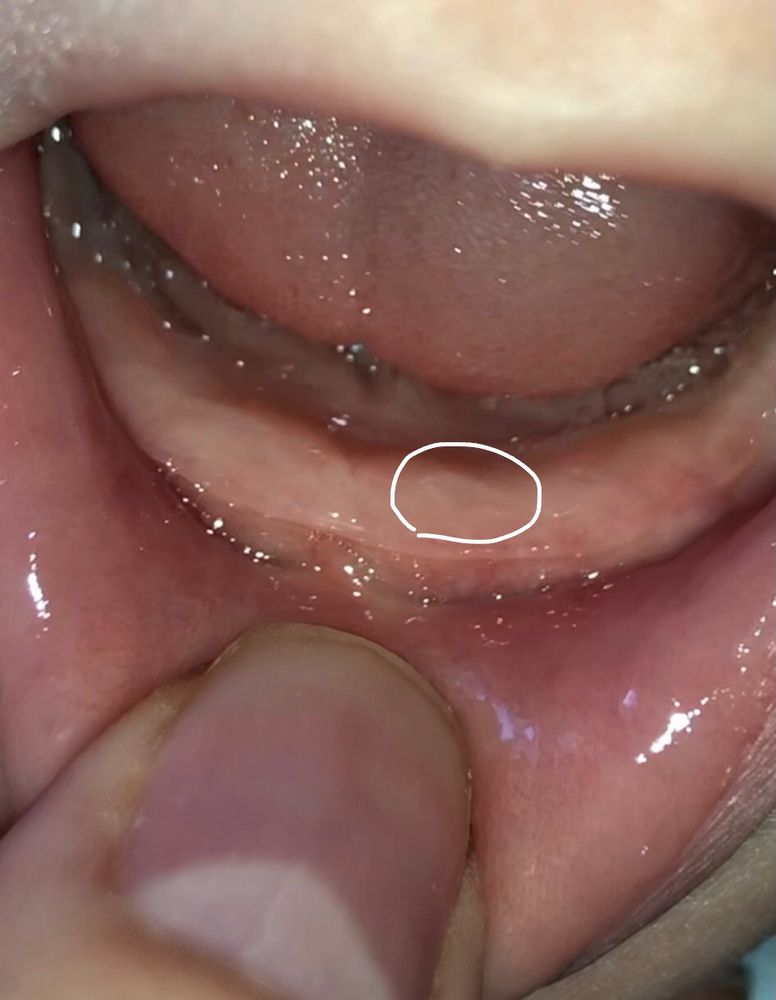

Irina Irina в Развитие от рождения до года 4 года Это зуб? Физическое развитие Посмотрите еще 20 записей на эту тему Отменить Ответить Baby Да 16.10.2021 Ответить Анна Да, десна истончается в месте выхода зубика) 16.10.2021 Ответить Раиса) Похоже ) 15.10.2021 Ответить Алина Да, очень похоже на то 15.10.2021 Ответить Во сколько ребёнок сел и пошел сам 8 месяцев Роману Чаты Беременных Выберите чат: Январята-2026 Февралята-2026 Мартята-2026 Апрелята-2026 Майчата-2026 Июнята-2026 Июлята-2026 Августята-2026